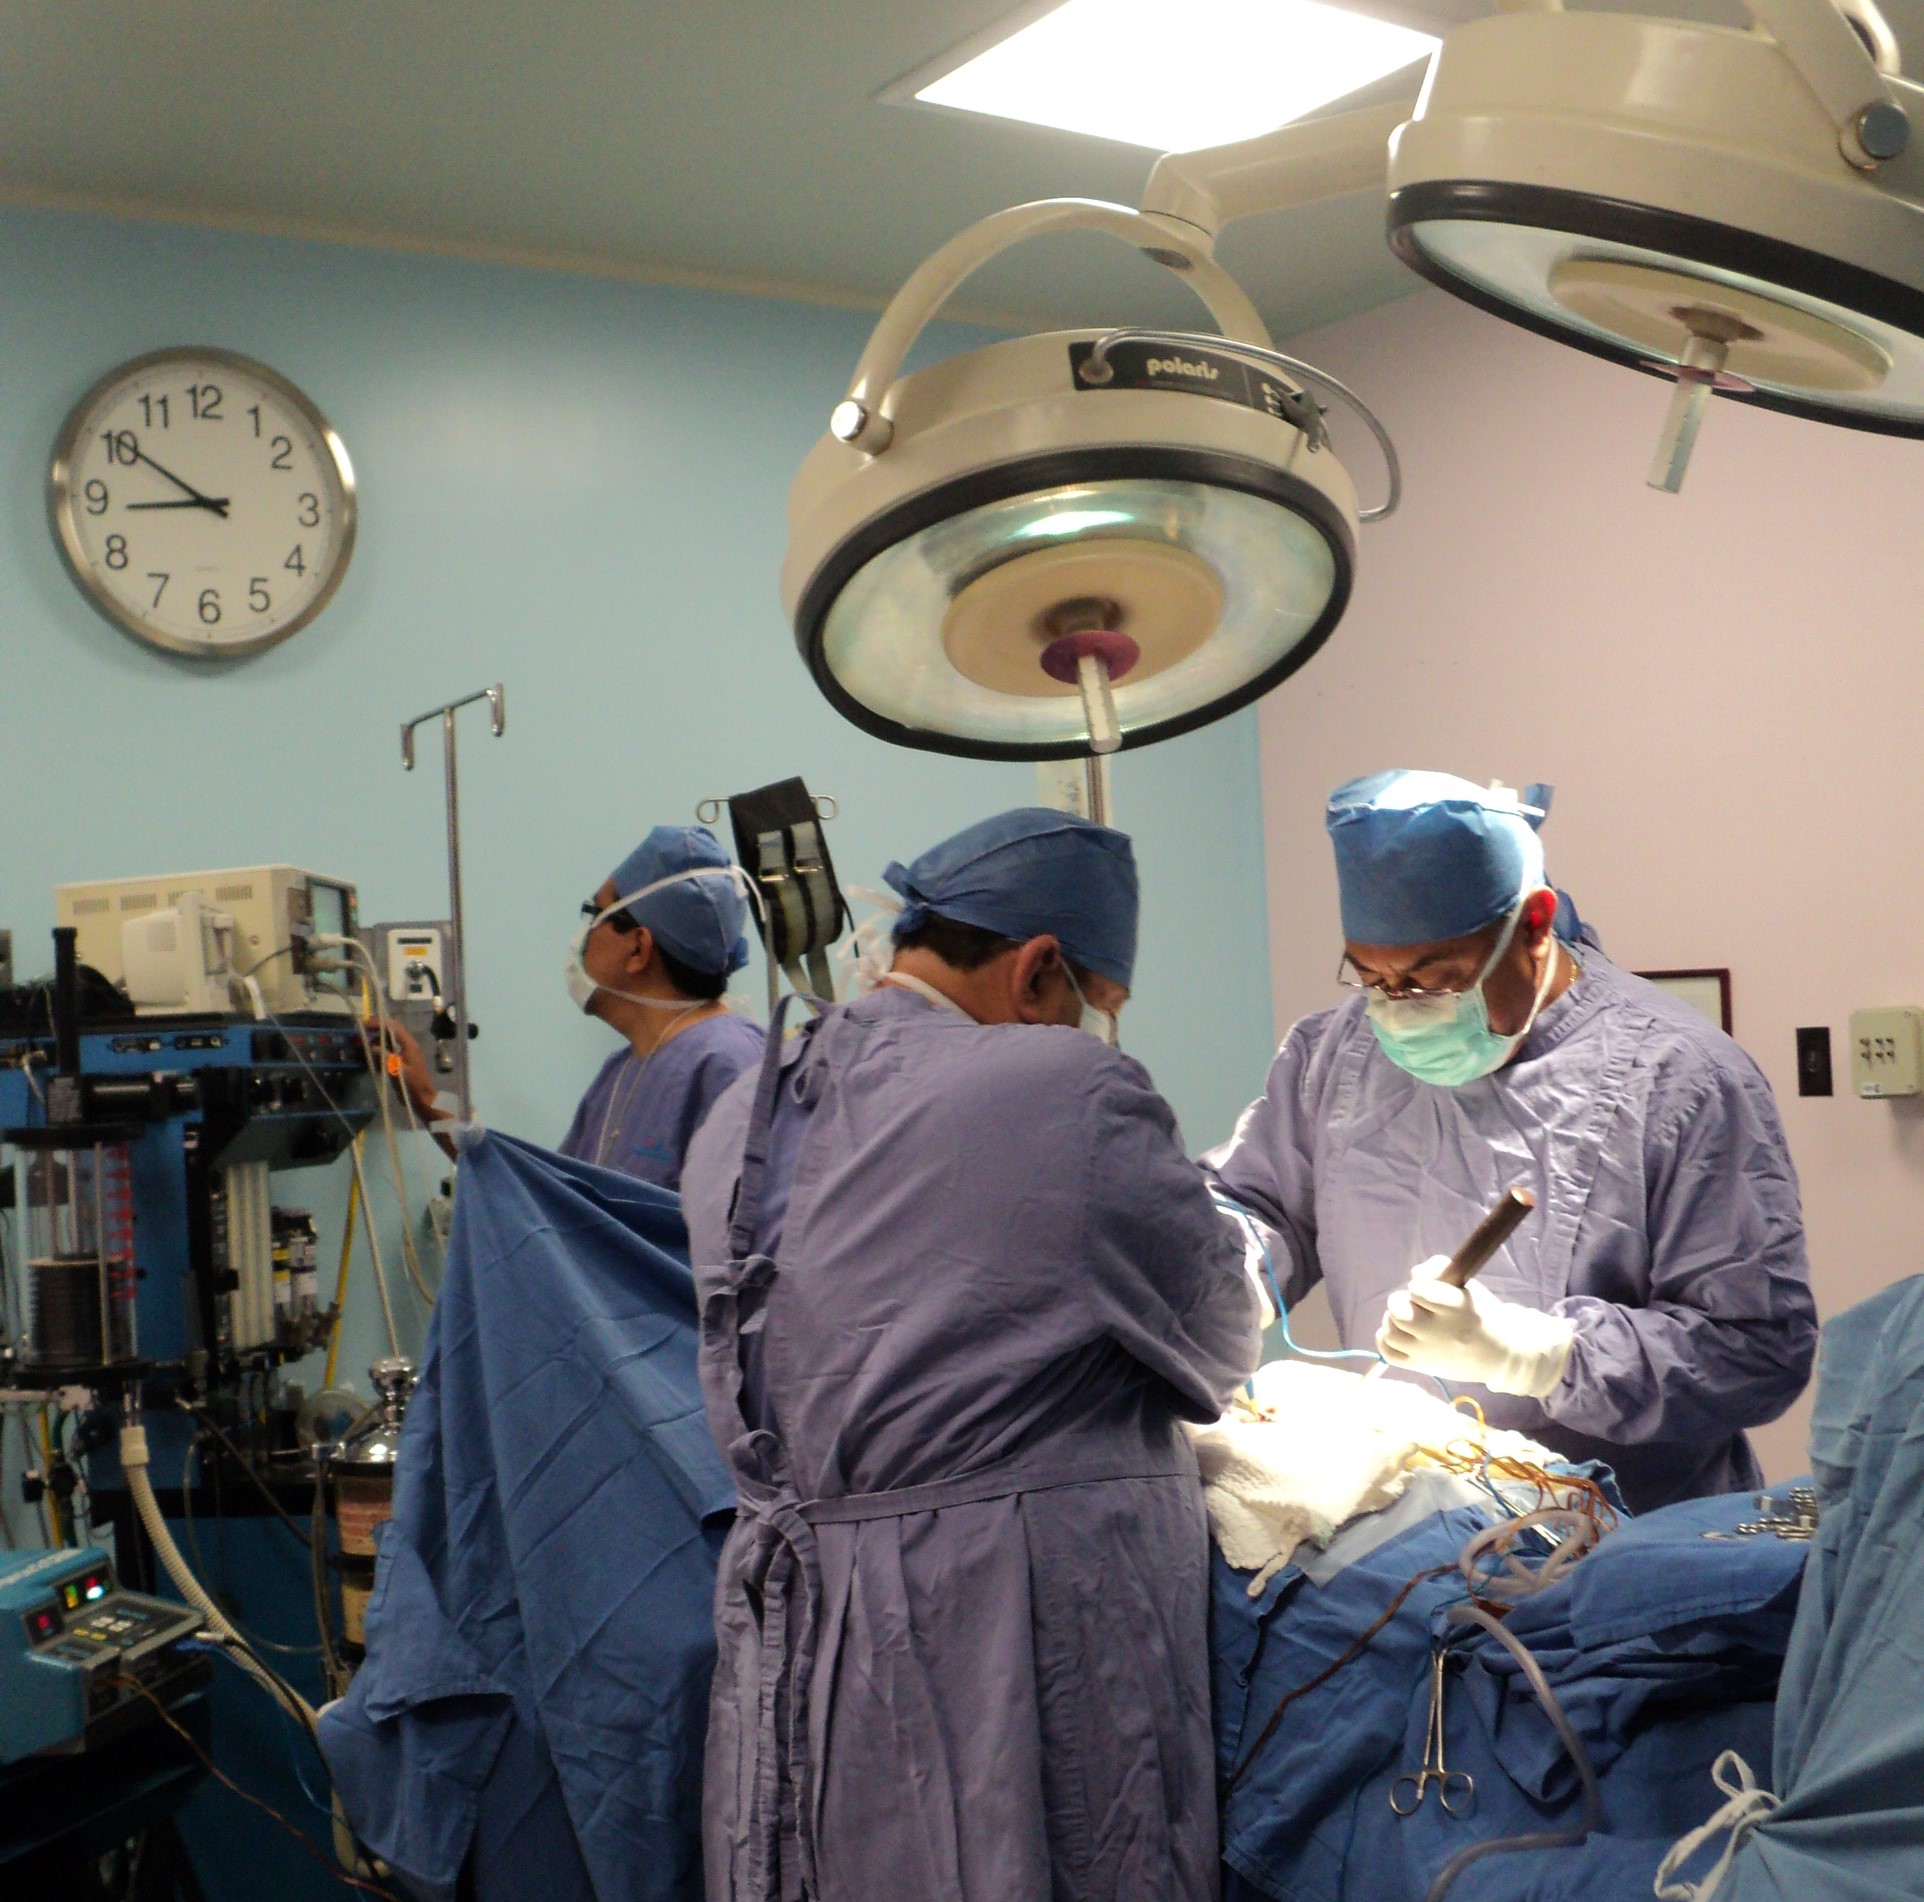

Contamos con médicos certificados especialistas en columna, rodilla, hombro, miembro torácico, mano, cadera, miembro pélvico, pie, lesiones deportivas, artroscopia, prótesis musculares, artritis reumatoide, rehabilitación, fisioterapia, ortopedia pediátrica con tecnología de vanguardia.